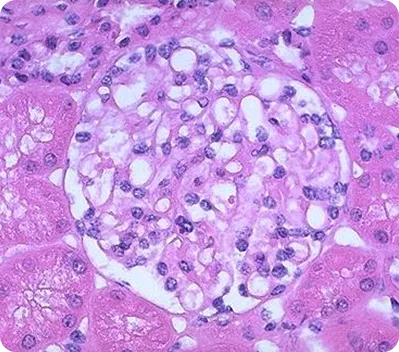

В настоящее время иммунофлюоресценция является неотъемлемой частью морфологического анализа прижизненного анализа почечной ткани. Такие заболевания, как IgA-нефропатия, C1q- и C3-гломерулопатии, не могут быть диагностированы без использования данного метода. Важным аспектом является локализация, а также выраженность свечения иммунных депозитов. Прямая иммунофлюоресценция на свежезамороженных тканях является наиболее широко используемым методом, позволяющим произвести качественную оценку депозитов и менее точный количественный анализ. Метод иммунофлюоресценции на парафиновых блоках, по данным литературы, может быть более информативным за счет точной количественной оценки иммунных включений. Однако данный метод ограничен в использовании в связи с техническими ограничениями морфологических центров10. Широкий спектр различных моноклональных антител к маркерам (IgG, IgM, IgA, C3c, С4d, C1q; легким цепям лямбда и каппа, и другие) позволяет в результате комплементарного связывания определить доминирующий вид депозитов и их локализацию.

Image